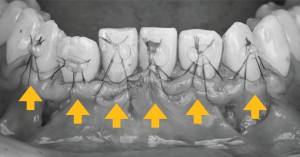

※初診時の口腔内写真正面

下あごの前歯部において、**複数の歯で歯ぐきが下がっている状態(歯肉退縮)**を認めました。

この部位は、もともと歯ぐきや骨の厚みが薄いことが多く、歯ぐきが下がりやすい傾向があります。

また、歯みがきの力のかかり方や歯並び、かみ合わせ、生活習慣など、さまざまな要因が関係していることがあります。

複数の歯に歯肉退縮がみられる場合には、歯ぐき全体の状態や原因を確認したうえで、適切な治療方法を検討することが重要です。

※下顎前歯の拡大写真

下あごの前歯部に注目すると、黒い線で示した部分が歯の上の部分(歯冠)と根の部分(歯根)の境目になります。

この境目よりも歯ぐきが下がっている状態がみられ、歯ぐきの退縮が起こっていることが確認できます。

※歯肉退縮量の測定

今回は、複数の歯で歯ぐきが下がっている状態がみられたため、専用の器具(プローブ)を用いて、それぞれの歯の歯ぐきの下がり具合を測定しました。